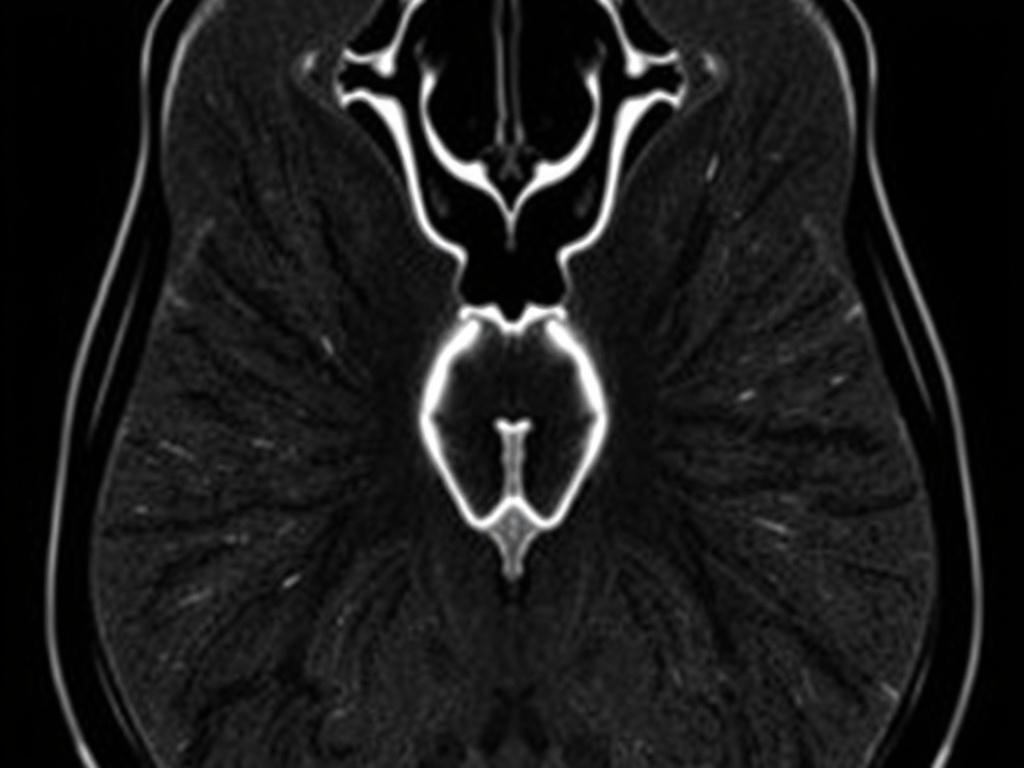

МРТ — это метод визуализации, где используются магнитное поле и радиоволны. В отличие от рентгена, здесь нет ионизирующего излучения. Для обследования предстательной железы применяются специальные режимы сканирования, которые показывают структуру органа, зоны с нарушенным кровотоком и подозрительные участки. Современная МРТ дает довольно детальную картину, особенно при использовании контраста и специализированных последовательностей.

Радиолог оценивает несколько ключевых параметров: размер и форму предстательной железы, структуру ткани, наличие узлов или очагов, прорастание в капсулу и соседние органы, а также состояние семенных пузырьков. Важная часть — оценка диффузионных и перфузионных характеристик, которые показывают, как вода и кровь движутся в ткани. Раковые очаги часто выглядят иначе в этих режимах.